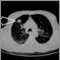

Chest CT; CT scan - lungs; CT scan - chestDefinition Return to top

Thoracic CT is a computed tomography scan of the chest and upper abdomen.